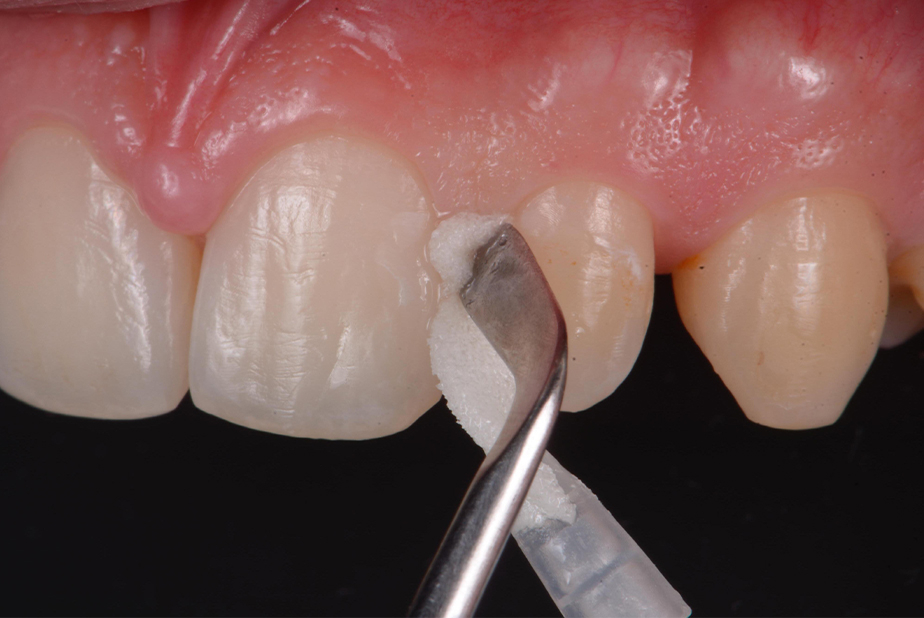

Prima dell’applicazione, è fondamentale detergere accuratamente la superficie dentale al fine di rimuovere la pellicola acquisita mediante ipoclorito di sodio al 2% per 20 secondi e quindi risciacquare e asciugare (Fig. 1). Successivamente è necessario rimuovere eventuali depositi inorganici, mordenzando con Acido Ortofosforico al 35-37% per 20 secondi. Una volta terminato, aspirare e risciacquare (Fig. 2).

Fig. 1 - Rimozione della pellicola organica acquisita con Ipoclorito di sodio al 2% (Da: G. Sammarco. Cariologia Clinica. Quintessence publishing Italia, 2025).

Per applicare il prodotto sulla lesione, isolare l’elemento da trattare con dei semplici rulli di cotone (non è richiesto l’utilizzo della diga di gomma) e distribuire il prodotto uniformemente sulla lesione, premendo bene la spugnetta in modo da far uscire il liquido, anche esercitando una pressione sull’applicatore mediante uno strumento quale una spatola di Heideman (Fig. 3). Grazie alla sua capacità di penetrare nelle microporosità e alla sua elevata affinità per l’idrossiapatite, il peptide riesce a raggiungere i siti danneggiati all'interno dello smalto demineralizzato fino alla profondità della lesione. Così, nel caso di lesioni cariose iniziali prossimali, è sufficiente premere la spugna dal lato buccale e linguale della zona prossimale. Poi, lasciare agire per circa 5 minuti la soluzione, al fine di permettere al peptide di auto-assemblarsi e formare la matrice peptidica che guiderà la remineralizzazione. Al termine del periodo di posa, il paziente può essere dimesso con la raccomandazione di non bere e non mangiare per circa 30 minuti.

Fig. 3 - Applicazione di CURODONT™ REPAIR (Da: G. Sammarco. Cariologia Clinica. Quintessence publishing Italia, 2025).